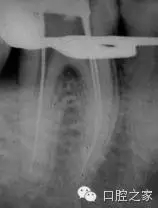

為了能夠直觀的確定額外牙根的存在,需要不同角度的X線投照來顯示。在下頜第一磨牙的根管治療過程中,最初的分角線投照是十分必要的(圖1a)。首先,使用根管銼來定位額外牙根,從表觀上類似穿孔的表現(xiàn)。如果根尖片所示不是非常確定,根尖定位儀能夠提供有效的、可信賴的信息來進行鑒別診斷,從而確定額外根管的存在。Walker和Quackenbush 總結(jié)了對咬合翼片的簡單分析可以探查到90%的病例中的遠中舌根。

在1990年,Carlsen 和 Alexander 就曾經(jīng)報道了398例下頜第一恒磨牙舌側(cè)額外牙根的研究。舌側(cè)額外牙根的宏觀結(jié)構(gòu)在根管形態(tài)和彎曲度上表現(xiàn)出高度變異性。當?shù)谌栏奈恢迷陬a側(cè)時,被稱之為副磨牙。其根管形態(tài)和彎曲度有非常高的變異度(圖1b)。典型的代表是,牙根的軸朝向磨牙的頰側(cè)。基于此,選擇遠中頰尖作為參考指示點,相對于經(jīng)典的選擇遠中舌根作為參考點更為容易些??紤]到根管口與根尖1/3的頰側(cè)曲度之間所形成的斜率,這些都表明是高度復雜的根管,不利于根管預備與根管化學沖洗。為了避免出現(xiàn)意外事故,推薦使用小號的、高度彈性的根管銼來通暢根管,預備根尖部。